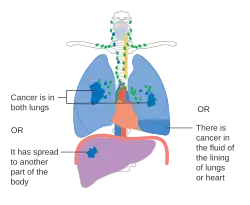

Stage IV lung cancer

Stage IV lung cancer